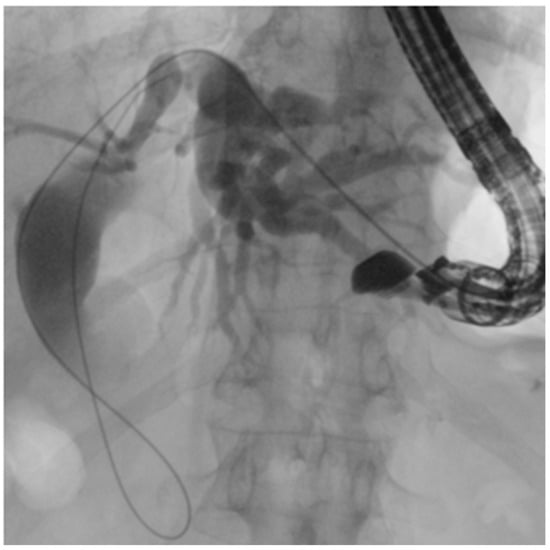

Figure 9. EUS-guided duodenojejunal anastomosis (EDEE): (A) EUS-guided deployment of a LAMS into the jejunal lumen; (B) use of a pediatric colonoscope to reach the biliojejunal anastomosis through the LAMS (indicated by the green arrow); (C) fcSEMS protruding from the anastomosis.

5.3.5. EUS-Directed Transenteric ERCP (EDEE)

In 2014, the first case of a trans-enteric duodeno-jejunal bypass by using a lumen-apposing metal stent (LAMS) to facilitate biliary access in Roux-en-Y hepaticojejunostomy was published [54]. To date, after more than ten years, EDEE is a consolidated and well-documented technique that represents a valid therapeutic option in patients with altered anatomy, although relegated to tertiary referral centers with experience in this type of procedure.

In this technique, a LAMS is used to create an anastomosis between the stomach or duodenum and the afferent biliary limb, thus restoring endoscopic access to the biliary anastomosis with a standard duodenoscope.

By providing a permanent and reusable access route, the entero-enteric bypass enables repeated interventions over time with standard devices. Moreover, the possibility to reach directly the anastomotic area with large-caliber scopes (e.g., pediatric colonoscope with 3.8 mm operative channel) also permits treatment of the most challenging cases with the full standard equipment (Figure 9).

The largest case series published, and subsequent expanded follow-up, report a technical success above 95% and long-term clinical efficacy above 90%. AEs included stent migration, bleeding, and leaks but were largely manageable. Compared with EA-ERCP, entero-enteric bypass is more durable and facilitates reintervention; compared with PTBD, it avoids external drains and improves quality of life [55,56].